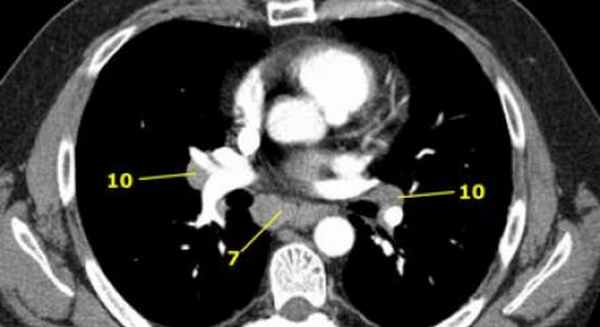

7. Подкаринальные лимфатические узлы

Эти лимфатические узлы расположены ниже уровня бифуркации трахеи (карины), но не относятся к нижнедолевым бронху и артерии. Справа они располагаются каудальнее нижней стенки промежуточного бронха. Слева они располагаются каудальнее верхней стенки нижнедолевого бронха.

Слева лимфатический узел 7 группы справа от пищевода.

10. лимфатические узлы корня легкого

Лимфатические узлы корня расположены проксимальнее долевых узлов, но дистальнее медиастинальной дупликатуры и узлов промежуточного бронха справа.

Все лимфатические узлы 10-14 групп являются N1 узлами, так как они находятся вне средостения.